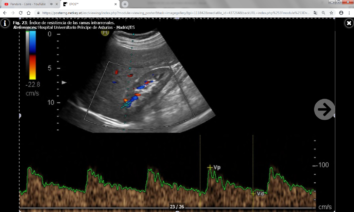

Los parámetros indirectos tienen una alta especificidad pero muy baja sensibilidad, y son los siguientes:

- Índice de resistencia (IR) : Es el resultado del cociente VPS – VTD / VPS (siendo VPS la velocidad picosistólica y VTD la velocidad al final de la diástole). Se debe calcular una media con las distintas medidas obtenidas en cada riñón y valorar si existen diferencias entre un riñón y el contralateral. Lo normal es que el índice de resistencia esté entre 0.6-0.7 y que la diferencia entre ambos riñones sea menor del 5% (ó 0.05). Un aumento de la velocidad telediastólica mayor de 150 cm/s en un paciente con IR intrarrenal menor de 0.7 es altamente sospechoso de estenosis mayor del 80%.

El IR no solamente permite detectar la presencia de estenosis significativas, sino que además predice el pronóstico y la respuesta al tratamiento de revascularización: En un estudio se publicó que en pacientes con IR mayores de 0.8 había escasa respuesta al tratamiento de revascularización ya que la enfermedad renal estaba establecida y era irreversible. No obstante, estos datos han sido ampliamente discutidos en la literatura y no existe acuerdo a día de hoy. - Tiempo de aceleración (TA) e índice de aceleración (IA) : Son parámetros más operador dependientes y por ello menos fiables que el IR. Los valores normales son menores de 0.07-0.08 ms y menores de 3 m/s respectivamente.